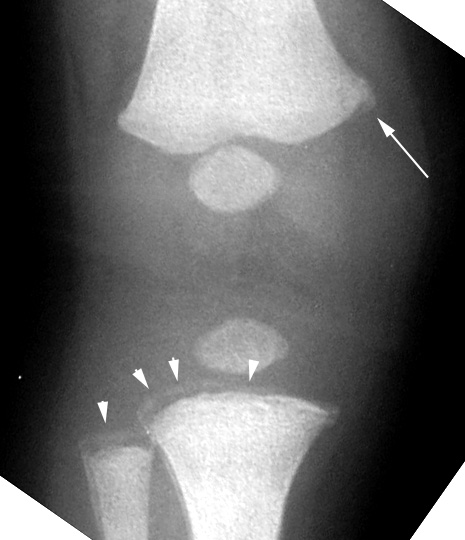

Tibia and fibula: arrowheads point to fracture that runs across metaphyseal width - bucket handle appearance. Arrow points to corner fracture of distal femur.

Femur: metaphyseal lipping of distal femur - corner fracture